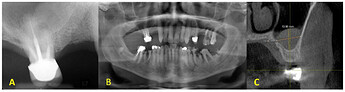

Preoperative radiographic evaluation: (A ) homogenous solitary radiopaque mass observed on the right sinus floor in intraoral periapical with a periapical lesion on the MB root of the right maxillary molar; (B ) a panoramic radiograph prior to initial therapy; (C ) CBCT cross-sectional view of mucocele/antral pseudocyst with a patent osteomeatal complex.